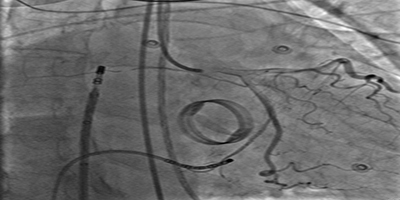

Successful Biventricular Pacemaker Implantation via Right Iliac Vein Route